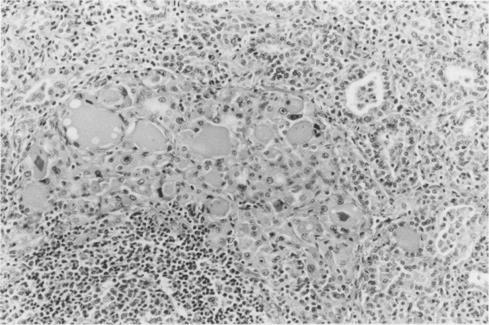

A case of autoimmune thyroiditis after long term treatment with lithium is described in a 29 year old Japanese woman with manic depression. Positive serum antithyroglobulin and antimicrosomal antibodies, diffuse goitre, and microscopic chronic thyroiditis, as well as the clinical history of long term lithium treatment were suggestive of lithium associated autoimmune thyroiditis. Microscopically, there was a mild degree of interstitial fibrosis and a moderate degree of lymphocytic infiltration. Some areas showed a moderate degree of stromal fibrosis and atrophic thyroid follicles. Lymphoid follicles with germinal centres, disrupted thyroid follicles with lymphocytic infiltration, and Hürthle cells were also observed. The differential diagnosis in patients presenting with these histological features includes painless (silent) thyroiditis, autoimmune thyroiditis and lithium associated autoimmune thyroiditis. A detailed clinical history is essential if the correct diagnosis is to be reached.

一名患有躁郁症的29岁日本女性,在长期接受锂治疗后出现了自身免疫性甲状腺炎。血清抗甲状腺球蛋白和抗微粒体抗体呈阳性、弥漫性甲状腺肿、显微镜下的慢性甲状腺炎以及长期锂治疗的临床病史提示为锂相关性自身免疫性甲状腺炎。显微镜下可见轻度间质纤维化和中度淋巴细胞浸润。部分区域显示中度间质纤维化和萎缩性甲状腺滤泡。还观察到有生发中心的淋巴滤泡、淋巴细胞浸润的破裂甲状腺滤泡以及许特莱细胞。具有这些组织学特征的患者的鉴别诊断包括无痛性(寂静性)甲状腺炎、自身免疫性甲状腺炎和锂相关性自身免疫性甲状腺炎。若要做出正确诊断,详细的临床病史至关重要。